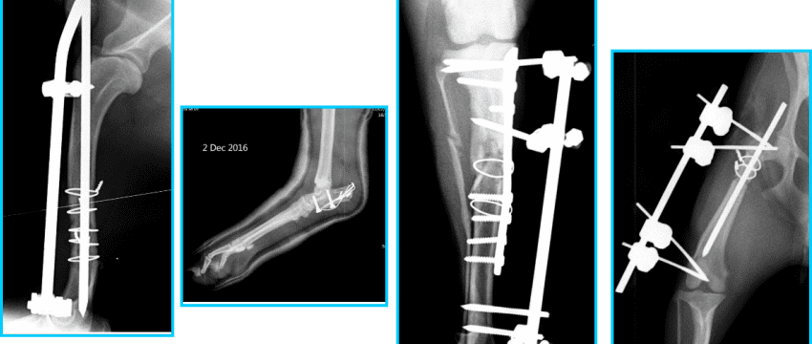

Để chẩn đoán chính xác tình trạng gãy xương, bác sĩ sẽ chỉ định thực hiện hình ảnh học, chủ yếu là X-quang. Kỹ thuật X-quang giúp phát hiện những gãy xương mà mắt thường không thể nhìn thấy. Nếu cần thiết, bác sĩ có thể sử dụng thêm các kỹ thuật hình ảnh khác như siêu âm hoặc chụp CT để thu thập thông tin chi tiết hơn về tình trạng xương và mô xung quanh. Từ đó, lược đồ điều trị sẽ được lên kế hoạch dựa trên kết quả chẩn đoán.

Gãy xương ở chó mèo là một tình trạng phổ biến, và việc điều trị thường yêu cầu các phương pháp phẫu thuật khác nhau để đảm bảo hồi phục tốt nhất cho thú cưng. Tại Phòng Khám Thú Y Dr.Vet, chúng tôi áp dụng một số phương pháp phẫu thuật hiện đại và hiệu quả để điều trị gãy xương, bao gồm nội soi, cố định xương bằng nẹp, vít, và những phương pháp khác.

Cố định xương bằng nẹp và vít là một trong những phương pháp truyền thống hơn. Kỹ thuật này bao gồm việc sử dụng các thiết bị cố định để giữ cho các mảnh xương trong vị trí chính xác. Phương pháp này có ưu điểm là sự ổn định cao và khả năng phục hồi mạnh mẽ, nhưng nhược điểm là cần một thời gian hồi phục lâu hơn và có nguy cơ nhiễm trùng tại vết mổ.